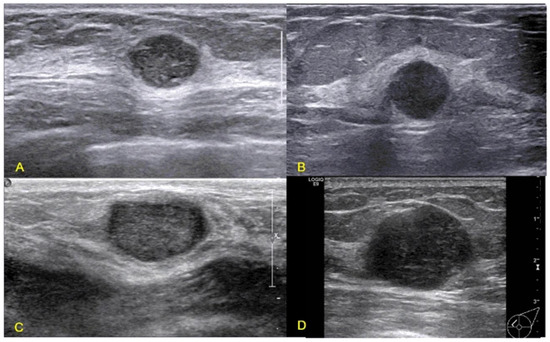

Advances in Medical Image Processing for Early Breast Cancer Detection: Classical Techniques and Deep Learning Perspectives

Breast cancer is the most common malignancy among women and a leading cause of cancer-related mortality, making early and accurate detection essential. This review summarises advances in breast imaging and computational diagnostics across mammography, ultrasound, and magnetic resonance imaging (MRI), highlighting challenges in [...] Read more.

Breast cancer is the most common malignancy among women and a leading cause of cancer-related mortality, making early and accurate detection essential. This review summarises advances in breast imaging and computational diagnostics across mammography, ultrasound, and magnetic resonance imaging (MRI), highlighting challenges in differentiating benign from malignant lesions and identifying rarer tumour types. Key preprocessing steps—denoising, deblurring, and contrast enhancement—are reviewed as they improve image quality prior to analysis. Classical methods (e.g., thresholding, edge detection, and region growing) are compared with deep learning approaches for segmentation and classification. CNNs, RNNs, and emerging transformer-based models consistently outperform handcrafted pipelines, with representative studies reporting 5–15% gains in AUC/accuracy and deep models achieving AUC > 0.85–0.95 on several benchmarks. The review also discusses dataset constraints, common evaluation metrics (AUC, Dice, sensitivity, specificity), and clinical translation barriers such as interpretability and domain shift. Overall, AI-driven methods show strong potential to enhance early detection and support improved breast cancer outcomes. Full article

Show Figures

Figure 1